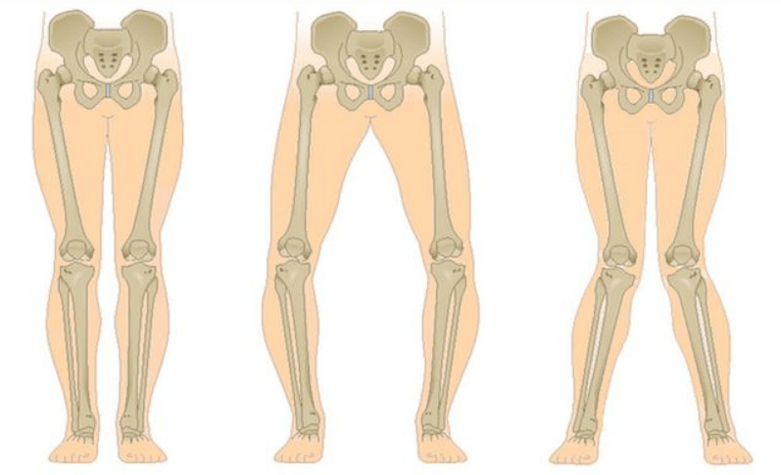

L'ultimo stadio della gonartrosi si distingue per il fatto che il dolore diventa quasi costante, causando ansia non solo mentre si cammina, ma anche a riposo e anche di notte, quando i pazienti devono cercare una posizione comoda per dormire. Il movimento è più limitato: è difficile piegare e stendere completamente la gamba. L'articolazione si deforma e aumenta di volume. Si osserva spesso deformità in valgo (a forma di X) o in varo (a forma di O) delle gambe. L'andatura diventa instabile e ondeggia. Nei casi più gravi sono necessari un bastone o delle stampelle.

A seconda del numero di articolazioni colpite si distingue la gonartrosi unilaterale e bilaterale.